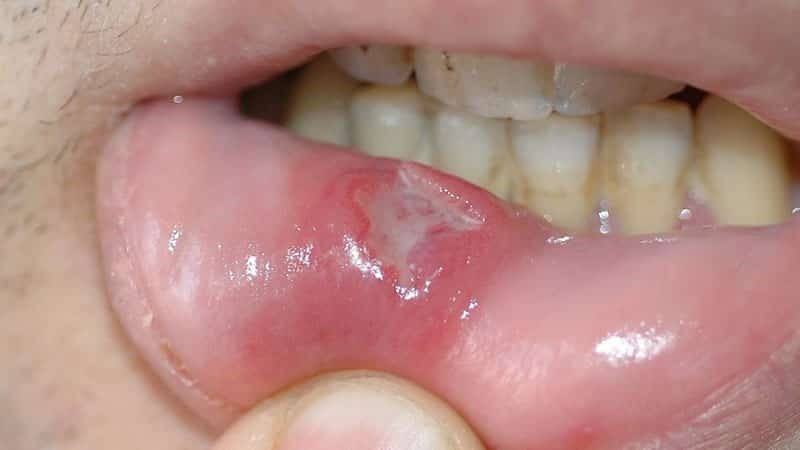

Злокачественное новообразование представляет собой длительно незаживающую язву эпителиального слоя слизистой оболочки рта и ретромолярной области.

- язвенный. Наиболее распространенная форма заболевания. Язвочки на слизистой не заживают, разрастаются, а кайма вокруг них краснеет. Контур рваный, а его края кровоточат.

Идентифицировать злокачественную язву от обычного стоматита во рту можно по отеку и припухлости щек, болезненности и постоянному дискомфорту даже в состоянии покоя. Насторожить должно длительное незаживление раны и ее кровоточивость.